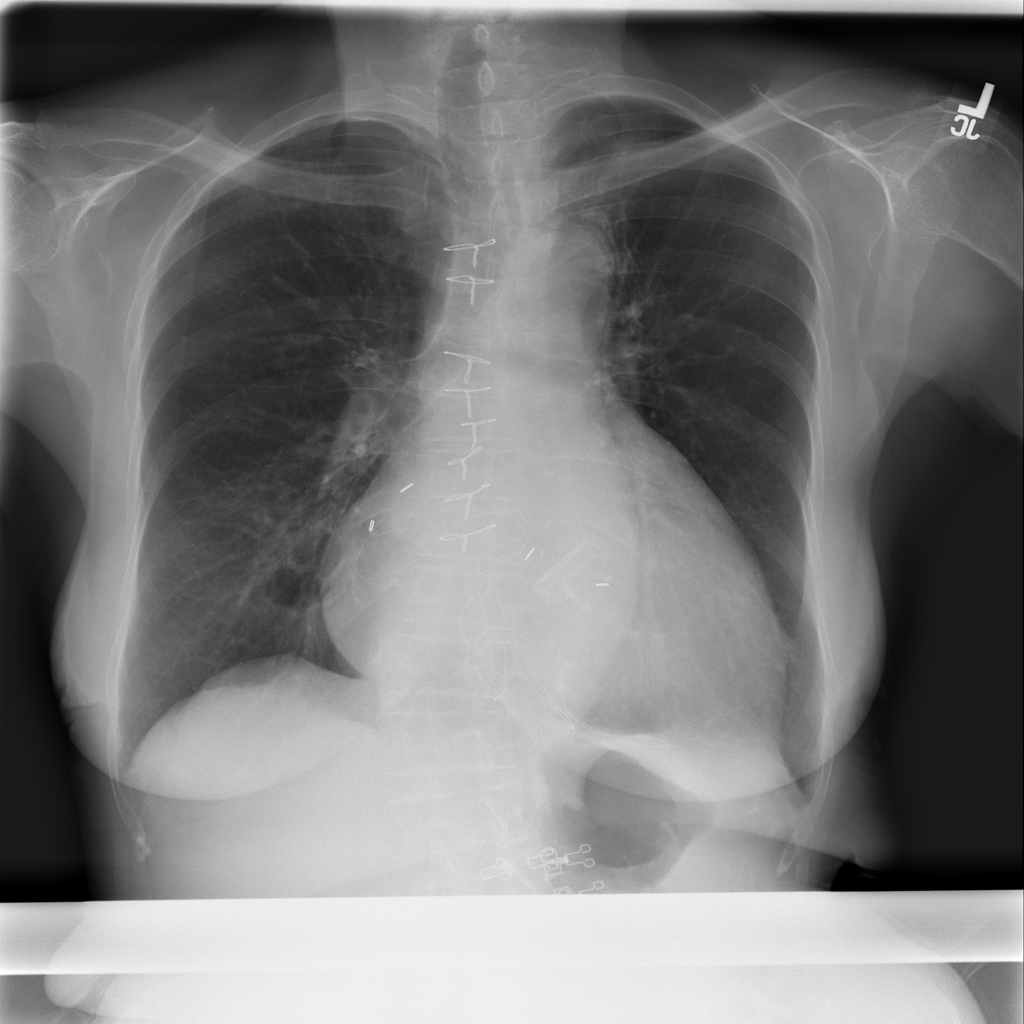

PAT-3384 · IMG-000Cardiomegaly

PAT-3384 · IMG-000

AP